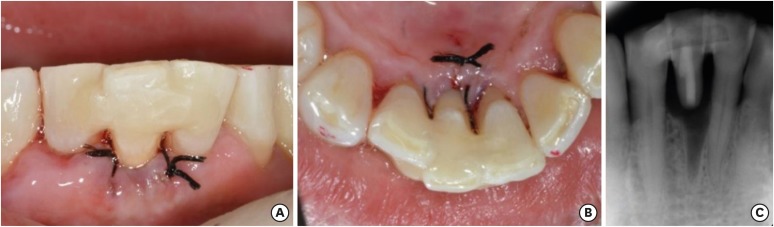

Figure 7

Postoperative view. (A) Intraoral photograph (labial view); (B) intraoral photograph (lingual view); (C) periapical view.

rde-45-e8-g007.jpg

First of all, to mark the gingiva level, a black dot was made on the labial and lingual surfaces of the tooth (Figure 2). Then, the coronal fragment and fractured root were extracted under local anesthesia (Figure 3). An access cavity for the coronal fragment was formed on the lingual surface of the tooth using a high-speed #330 bur (H7.314.008, Komet, Lemgo, Germany). The root canal was enlarged using a Gates-Glidden drill (MANI, Tochigi, Japan). Next, the coronal fragment was soaked in 5% sodium hypochlorite for 5 minutes. The root canal was filled with a resin-modified glass ionomer (Fuji II LC, GC, Tokyo, Japan) and polished using a white stone (Dura-White Stones, Shofu, Kyoto, Japan) and One-gloss (Midi, Shofu) (Figure 4). The coronal fragment was reinserted in the extraction socket and fixed temporarily using G-fix (GC) and a twisted wire (0.0215″ stainless steel wire, American Orthodontics, Sheboygan, WI, USA). The torn gingiva during root fragment removal was ligated with 4-0 black silk (AILEE, Busan, Korea) (Figure 5). Space for a reinforcing fiber was made using a high-speed tapered diamond bur (SF-12, MANI) on the middle of the lingual side from the mesial aspect of tooth #42 to the distal aspect of tooth #31, across tooth #41. The depth of the preparation was approximately 1.0 mm to make adequate space for the fiber and composite resin. The length of the cavity was measured using a Wedjet (Coltene/Whaledent, Alstatten, Switzerland) and Everstick C&B fiber (GC) was cut to that length (Figure 6). A 37% phosphoric acid gel (DenFil Etchant-37, Vericom, Anyang, Korea) was applied to the enamel for 20 seconds, rinsed off, and then gently dried. Singlebond Universal (3M ESPE, St. Paul, MN, USA) was applied to the enamel and dentin, dried gently for 5 seconds, then light-cured for 10 seconds using a LED curing light (G-Light, GC) A thin layer of flowable composite was placed on the preparation site and the fiber was inserted using hand instruments and then light-cured. Composite resin (Filtek Z-350 XT, 3M ESPE) was packed on the fiber and interproximal surface. Because of crowding of tooth #41, resin was packed on the buccal side of the pontic and adjacent teeth to reinforce the connector area. Areas of premature contact or lateral excursion contact on the pontic site were removed during occlusal adjustment. After occlusal adjustment using a diamond finishing bur, the surfaces were polished with One-gloss and an Astro-brush (Ivoclar Vivadent, Schaan, Liechtenstein) (Figure 7). The stiches were removed after 1 week.